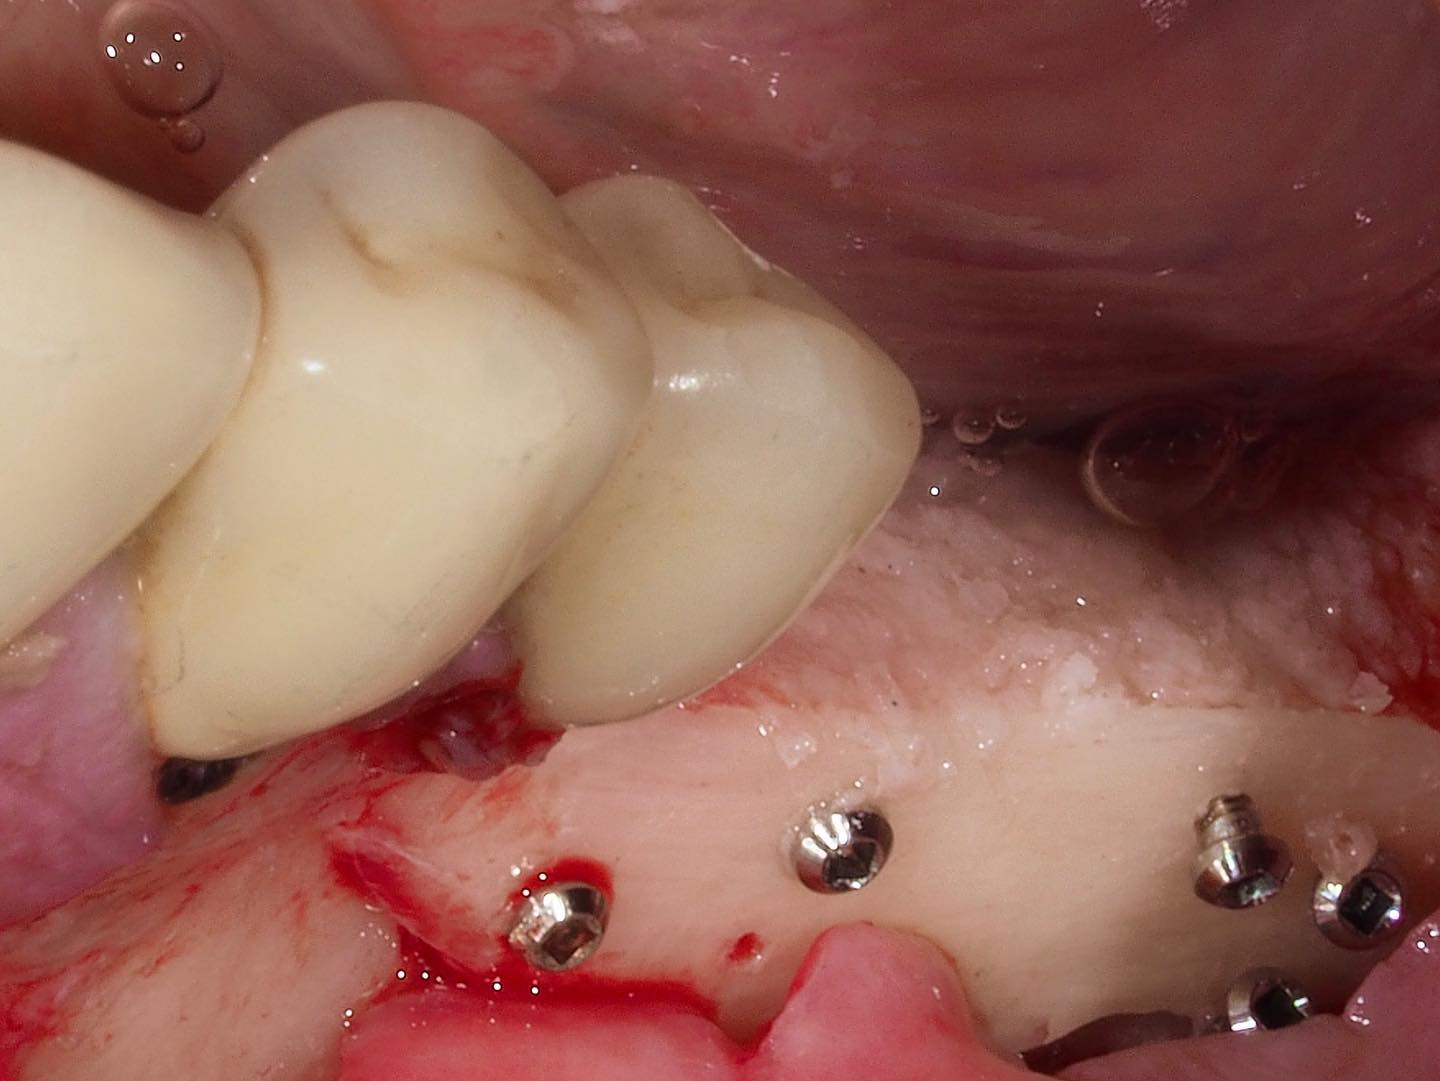

¿Sabías que en torno al 50% de los implantes que colocamos precisan procedimientos regenerativos previos o simultáneos a su colocación?

En este curso aprenderás TODO sobre Regeneración Ósea Guiada (ROG)... desde los principios biológicos hasta la técnica quirúrgica PASO A PASO.

Una